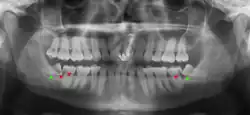

Impacted wisdom teeth are classified by their direction of impaction, their depth compared to the biting surface of adjacent teeth and the amount of the tooth's crown that extends through gum tissue or bone. Impacted wisdom teeth can also be classified by the presence or absence of symptoms and disease. Screening for the presence of wisdom teeth often begins in late adolescence when a partially developed tooth may become impacted. Screening commonly includes a clinical examination as well as x-rays such as panoramic radiographs.

If the tooth cannot be assessed with clinical exam alone, the diagnosis is made using either a panoramic radiograph or cone-beam CT. Where unerupted wisdom teeth still have eruption potential several predictors are used to determine the chance of the teeth becoming impacted. The ratio of space between the tooth crown length and the amount of space available, the angle of the teeth compared to the other teeth are the two most commonly used predictors, with the space ratio being the most accurate. Despite the capacity for movement into early adulthood, the likelihood that the tooth will become impacted can be predicted when the ratio of space available to the length of the crown of the tooth is under 1.[5]: 141

Screening

There is no standard to screen for wisdom teeth. It has been suggested, absent evidence to support routinely retaining or removing wisdom teeth, that evaluation with panoramic radiograph, starting between the ages of 16 and 25 be completed every 3 years. Once there is the possibility of the teeth developing disease, then a discussion about the operative risks versus long-term risk of retention with an oral and maxillofacial surgeon or other clinician trained to evaluate wisdom teeth is recommended. These recommendations are based on expert opinion level evidence.[19] Screening at a younger age may be required if the second molars (the "12-year molars") fail to erupt as ectopic positioning of the wisdom teeth can prevent their eruption. Radiographs can be avoided if the majority of the tooth is visible in the mouth.